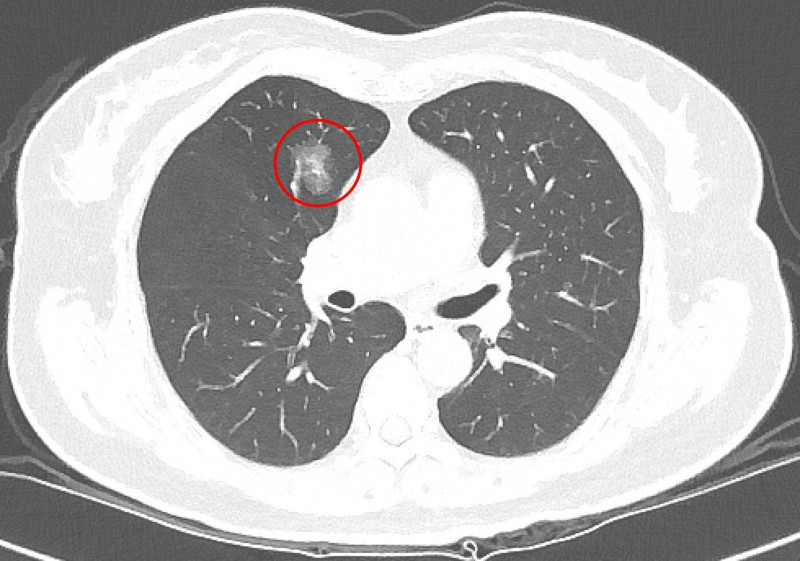

〔記者翁聿煌/新北報導〕隨著低劑量電腦斷層(LDCT)篩檢日益普及,越來越多民眾在健康檢查或就醫過程中發現肺部小結節,也讓「到底要不要立刻開刀」成為門診中常見疑問,台北慈濟醫院胸腔內科醫師吳智偉針對院內LDCT共6997名篩檢個案進行回溯性分析,結果發現手術切除的病灶中,有約3分之2被證實是惡性腫瘤,另外3分之1為良性腫瘤,由此可知小型肺部結節在影像判讀與切片診斷上極具挑戰,研究成果於今(2026)年元月獲國際期刊《International Journal of Medical Sciences》刊登。

吳智偉指出,肺癌發生率已居全國第一,影響因子包括抽菸、肺癌家族史及空氣污染等,但臨床上超過一半肺癌患者其實不抽菸,因此即使沒有抽菸習慣,也不能完全輕忽風險,近年政府積極推動低劑量電腦斷層篩檢,提升肺癌早期發現及治療的機會,針對肺部小結節,臨床上雖會依據大小、影像型態、生長狀況以及病人的臨床背景進行綜合判斷,但部分良性病灶在影像上與早期肺癌相似,有些早期惡性病灶則生長緩慢、不易立即判別。

吳智偉說明,許多肺部結節通常需要追蹤很長的時間,才會有些微變化(1年約長大0.1cm),臨床上會根據變化的型態進一步評斷處置方式,極早期的結節因為太小,無法經由穿刺切片確認屬性,他提醒,發現肺結節不必過度恐慌,也不代表一定要立刻動刀,目前國內外的共識是以大小0.8公分作為最基礎的判斷準則,在困難判讀的情況下,建議須定期追蹤,若在追蹤期間出現變大或影像特徵改變,建議與醫師討論或進一步評估手術時機,通常會有機會在零期或第一期及早治療。